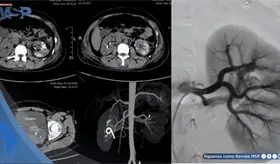

Las prótesis antiguas de metal con metal pueden liberar partículas microscópicas que generan inflamación severa, masas que imitan tumores malignos y, además, crean un ambiente propenso a infecciones profundas difíciles de tratar.